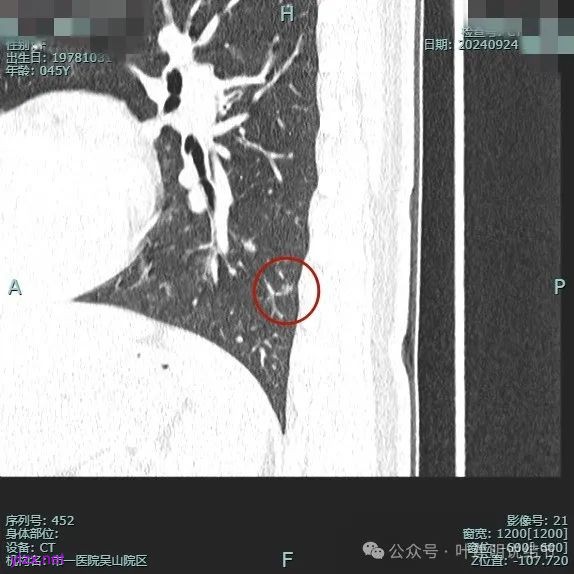

我们先来看2024年9月时的影像:

病灶1:

右下背段混合密度病灶,边上不太清爽,有片状淡磨玻璃影,实性部分密度较高。

感觉病灶有点晕征似的,表面不平,灶内不太致密。

有小血管进入,似有晕征。

离胸膜近但牵拉不明显,病灶边缘有细毛刺,较短且不太锐利。

边缘少许磨玻璃成分,血管进入明显。

瘤肺边界稍显不清。